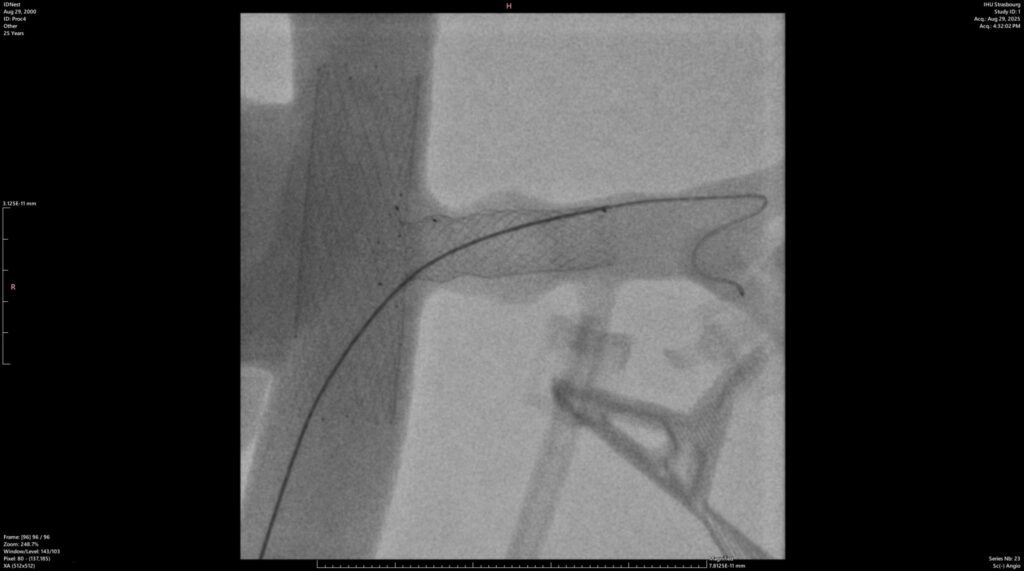

Access to the IHU’s state-of-the-art hybrid rooms allowed us to conduct a series of tests in near-real conditions. In total, 4 implantation procedures of our T-Stents were performed inside a dedicated in-vitro model, all under radiological control (X-ray).

The objective was clear: to validate the device’s visibility on imaging and confirm its maneuverability for the surgeon.

The results perfectly met our expectations. The tests confirmed excellent visibility of the products under X-ray (see image above) as well as great ease of use for the operators.